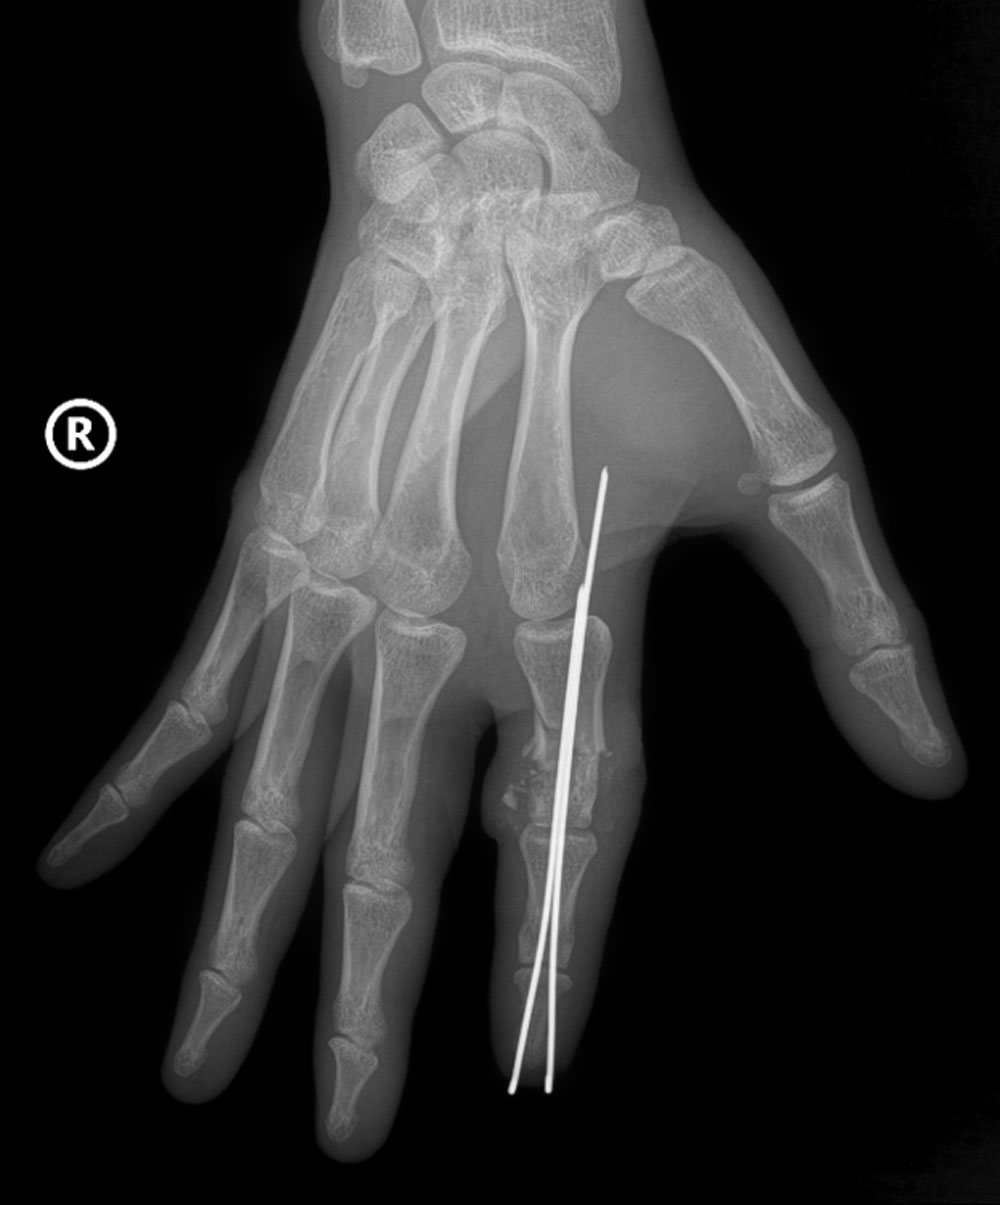

![]() |

|

Hình ảnh X-Quang phần ngón trỏ tay phải bị đứt rời của anh D được định vị và cố định bằng kim chuyên dụng. |

Tại phòng mổ, kíp phẫu thuật cấp cứu được triển khai với sự phối hợp đa chuyên khoa: vi phẫu tạo hình, gây mê hồi sức, chấn thương chỉnh hình… Hai kíp phẫu thuật được triển khai song song, một kíp làm sạch và chuẩn bị phần ngón đứt rời, kíp còn lại chuẩn bị phần mỏm cụt. Xương ngón được định vị và cố định bằng kim chuyên dụng để tạo trục vững, hệ thống gân và dây chằng được phục hồi. Đặc biệt là thần kinh và các mạch máu nhỏ li ti chỉ khoảng 0,8 - 1mm được phục hồi với độ chính xác cao dưới kính hiển vi phẫu thuật với dụng cụ đặc biệt nhằm đảm bảo phục hồi lưu thông tưới máu cho phần đứt rời.